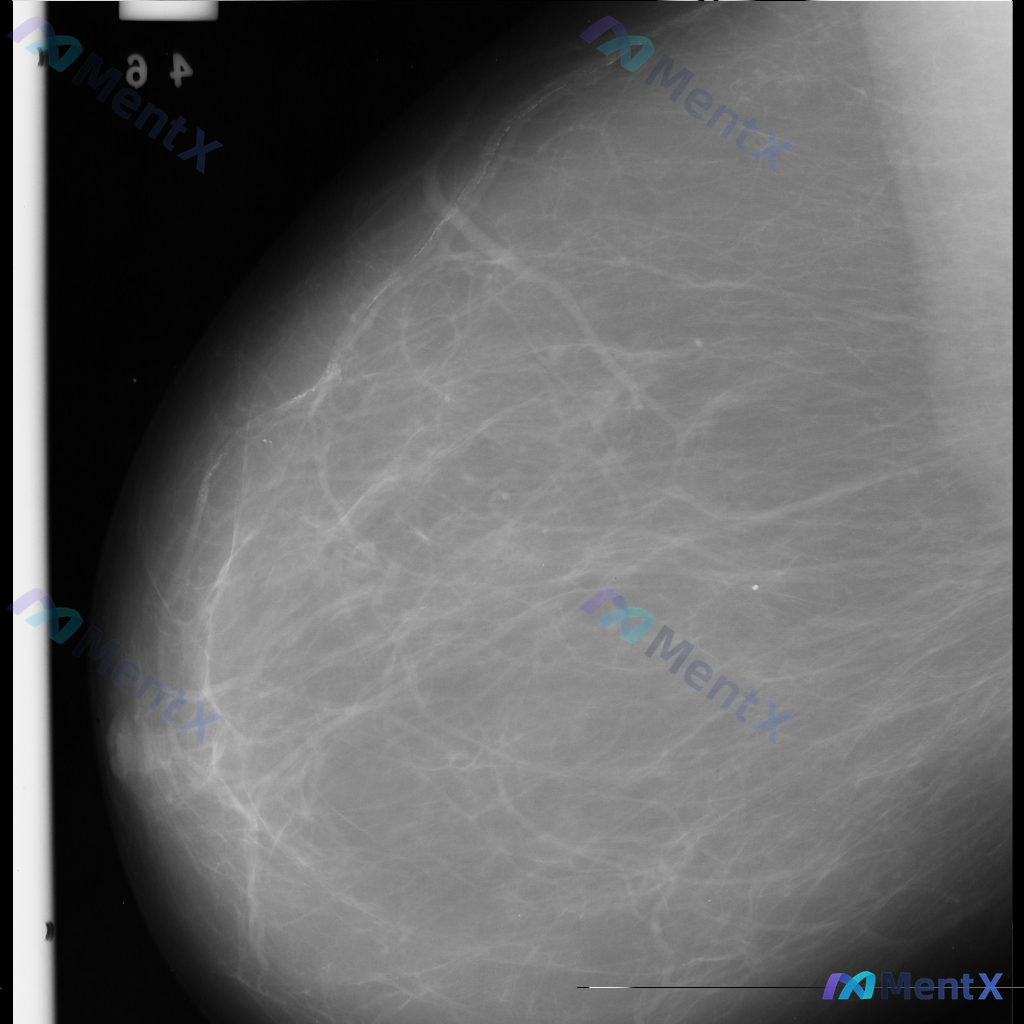

整理到一张乳腺钼靶影像资料,主要征象如下: - 图像中央偏右下方可见一处约5mm、密度相对较高的圆形或卵圆形致密影,边缘尚可; - 右上象限可见沿乳腺导管走行的一些粗大钙化影; - 中央偏下方也可见散在点状钙化,形态和分布无典型恶性特征; - 乳腺组织以纤维腺体为主,脂肪组织相对较少,属于致密影较多...